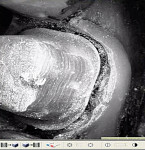

With the Lava software, users instantly see on the monitor what they recorded and have the ability to edit erroneous data with the software’s Smart Scan feature. The Occlusal Reduction Tool feature of the software helps dentists evaluate tooth preparation occlusal reduction. The scanning procedure can be completed in 2 to 5 minutes depending on the operator’s level of expertise, patient anatomy, patient compliance, and whether the scan target is a full arch or quadrant. This optical system requires that the teeth be completely coated with a thin layer of titanium oxide in a dry field while the positioned wand lens glides above them. There can be no contact with the powdered teeth, as this could result in powder residue being deposited on the wand lens, thus damaging the imaged data. The preparation finish line must be visible and not contaminated with blood or rotary instrumentation debris, nor should there be any overlaying crevicular soft tissue at the gingival crest.

Since the image modeling is a real-time video sequence, editing is simplified with Lava™Design 4.0 software, and the user can immediately evaluate and decide to rewind and scan more data if necessary. The preparation arch, opposing arch, and a lateral view of these arches in a position of maximum intercuspation must all be scanned to complete the file for the software program. The touchscreen feature easily allows all information entry as well as 360º virtual model manipulation. The margin-marking function allows the user to confirm the preparation finish line boundary with the viewing aid of either a 3-D model or individual photographic clips from the video file (Figure 2) before electronically sending the digital prescription and STL file to the Lava C.O.S. member laboratory. The STL file can be used to produce a plastic polymer die SLA model and opposing arch model through SLA with an accurate articulation. The early versions of STL file data were intended to mill a Lava zirconia substructure. The flexibility of the current Lava C.O.S. software, as well as the Cadent iTero software, allows for the scanning of any tooth preparation finish line design or an implant fixture level, digitally coded scan abutment.